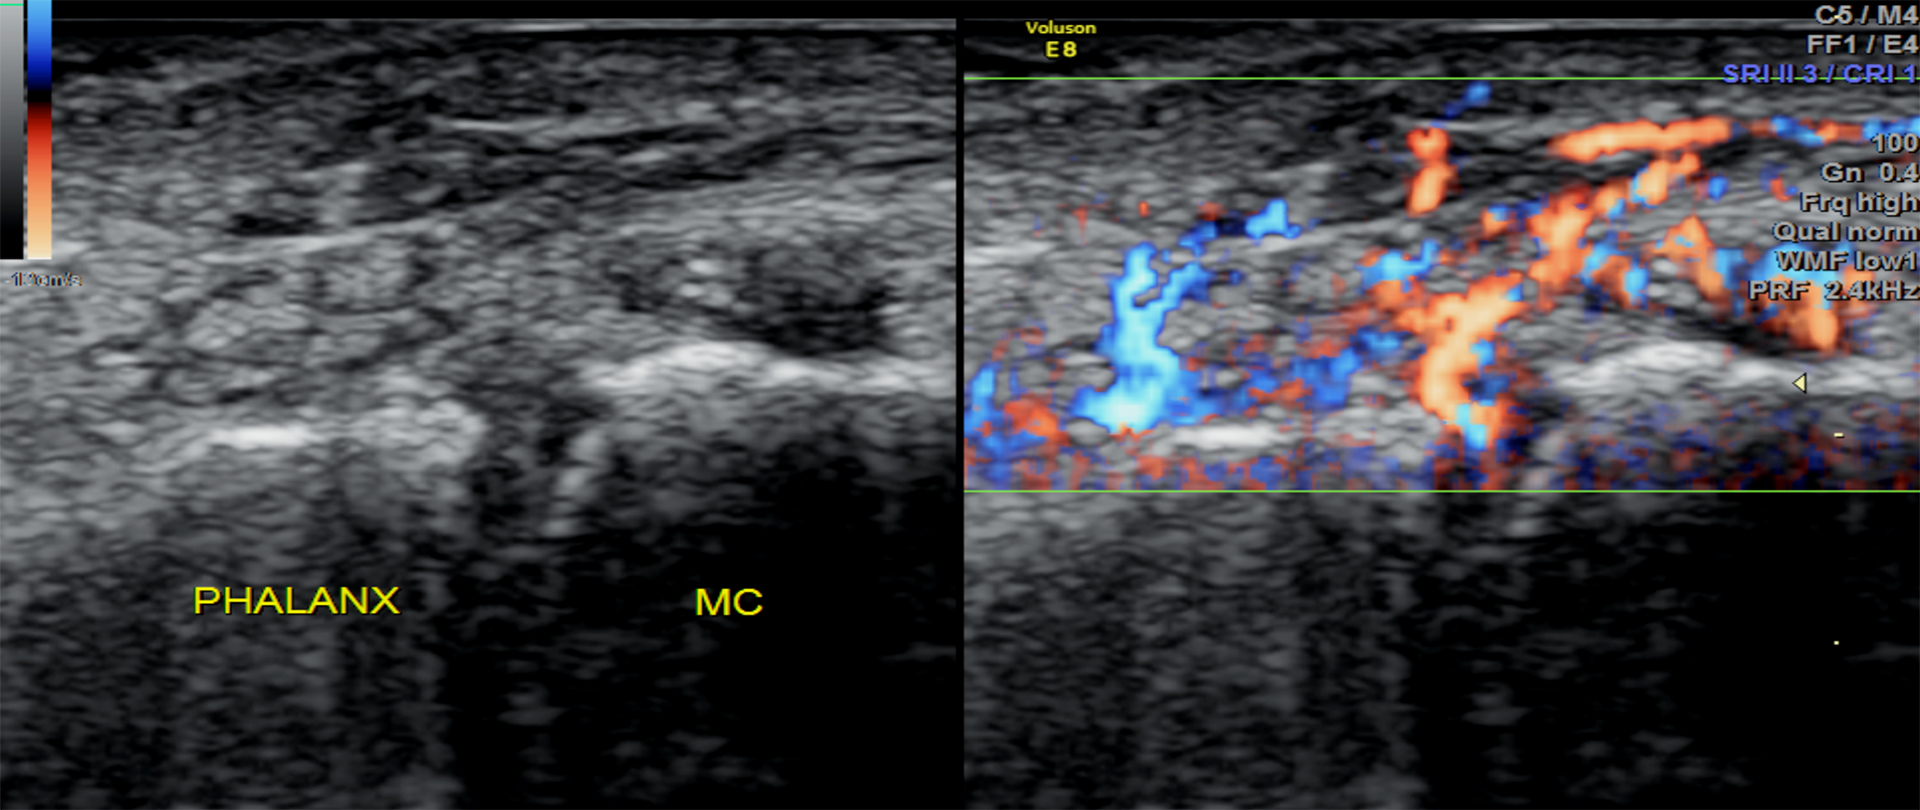

info.secretarymus@gmail.comThe recognition of MSK USG as a valuable clinical tool is neither automatic nor guaranteed. It is earned by maintaining quality control with positive results in clinical diagnosis, a goal that is obtainable only when high educational standards are met in the production of MSK sonographers and sonologists. The serious nature of MSK sonongraphy requires individuals who wish to become MSK sonographers to be exposed to both disciplines if they are to assume the responsibilities required of them in a quality MSK ultrasound setting.